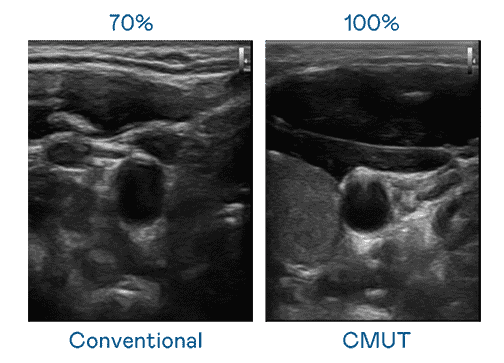

CMUT 技术是一种用电容式微机电元件来产生超音波讯号的技术。。与传统 PZT 压电式技术相比,,CMUT 频宽增加 30%,,,更宽频的超音波讯号让影像解析度大幅提升,,是实现高影像品质医疗超音波扫描、、、促进精准医疗发展的关键技术。。。。

大频宽带来超清晰影像

超音波影像的解析度高低,,首先取决于探头能发出的讯号频宽。。。。888.BY集团电子游戏 CMUT 可提供高清晰的超音波讯号,,提供高频宽、、、高灵敏度、、影像纹理细节更高的超音波影像,,协助医护人员缩短影像判读时间及利用精准的医疗影像进行诊断。。